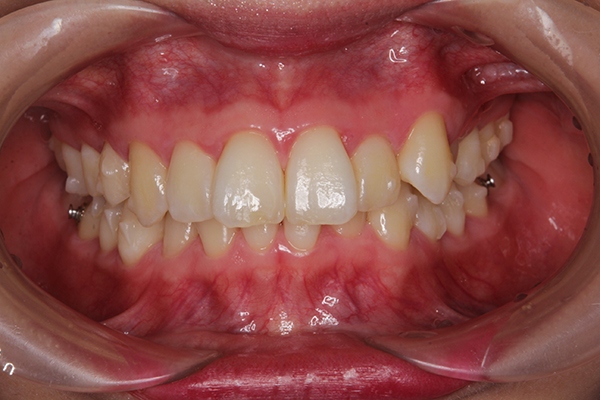

写真は、オルソパルスと、矯正開始から80日経過の口腔内写真です。

上の歯に隙間が空いていて、こうして見てみると面白いですね(笑)

下の歯の横の銀色のボタンは、顎間ゴムをひっかけるためのものです!